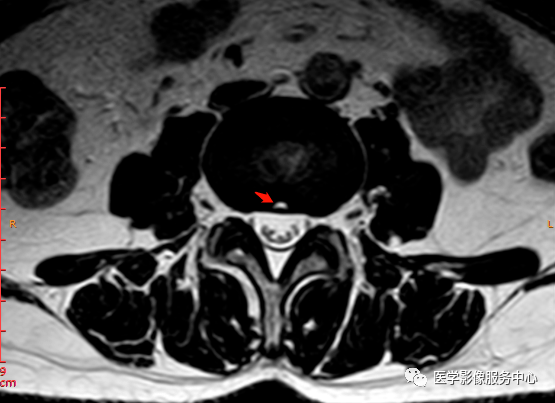

矢状位PD压脂序列

这个患者腰椎间盘膨出程度不明显,神经根没有明显的受压,椎管未见明显狭窄,那这个患者腰疼的“罪魁祸首”是腰椎间盘膨出嘛?

L3-4椎间盘后缘可见点状高信号区(红色箭头所指处)

红色箭头所指的异常信号区是是什么呢?平时工作中大家有没有遇到这种情况,你会不会忽略这个异常信号?有没有想过这个椎间盘后缘高信号区是引起患者腰疼的重要因素呢?下面为大家重点介绍。

影像表现主要在T2矢状位及T2横断位可见椎间盘前缘或后缘可见高信号区;

日常工作因腰腿疼痛来检查腰椎MRI的很多,而腰腿疼痛并不一定就是腰椎椎间盘突出或膨出导致的,我们应该需要知道椎间盘HIZ也会引起腰腿疼痛,这种椎间盘源性的疼痛我们不能“忽略”;椎间盘后方HIZ并不少见,椎间盘后方 HIZ 在 T2WI 的局限性高信号、T1WI 呈局限性较低或等信号意味着通常所指的纤维环破裂伴随肉芽组织长入;而 T1WI、T2WI 均呈高信号可能是钙化组织。